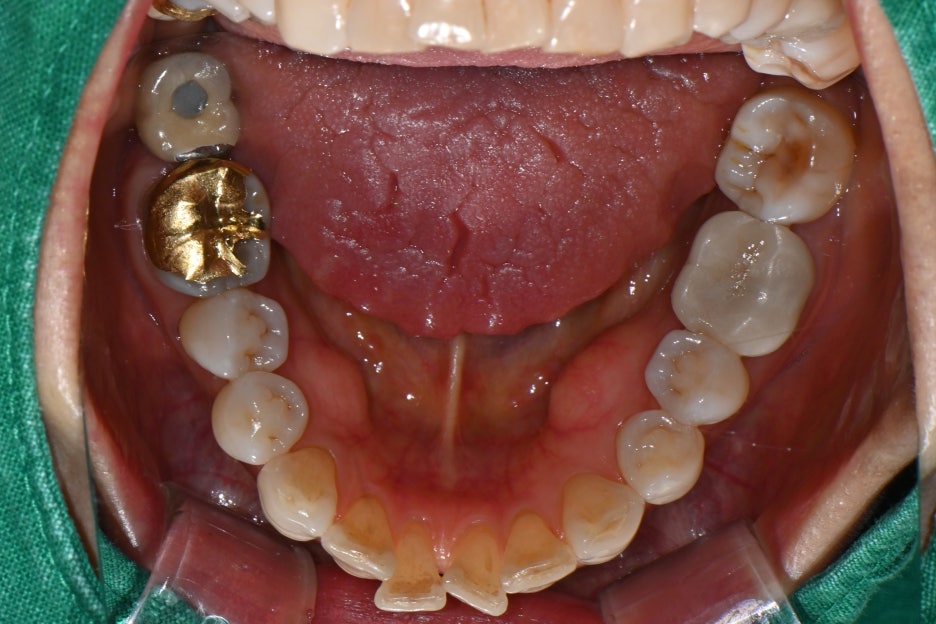

파노라마 엑스레이와 구강내 사진을 통해 확인한 결과,

왼쪽 위 두 개의 어금니가 파절 및 결손 상태

③ 보철물 제작 및 장착

– 치과 내 기공소에서 환자분의 다른 치아 색상과

어울리도록 맞춤 지르코니아 크라운을 제작했습니다.

– 교합(물림)을 조정하여 자연스럽고

편안하게 씹을 수 있도록 장착했습니다.

치료 전 후 사진